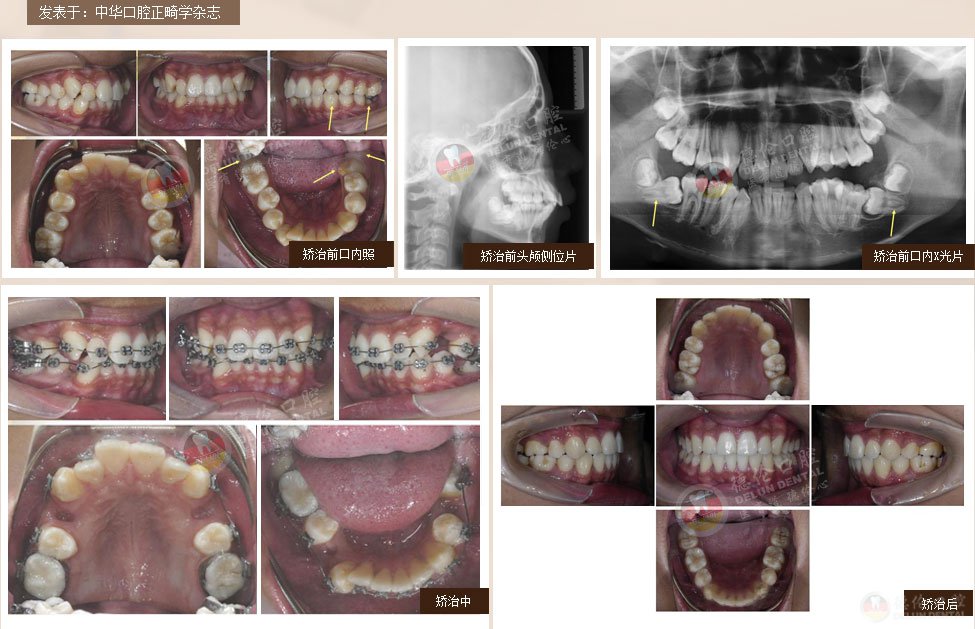

案例2:女 24岁

牙齿症状:牙列不齐、下颌第二、第三磨牙水平阻生,左侧磨牙锁牙合

矫治方法:拔除上颌及右下第一双尖牙,左下第二双尖牙以及2个下第三磨牙